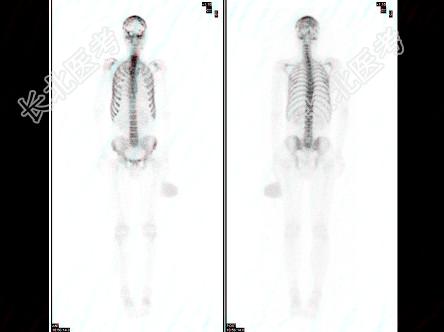

- 多项选择题男性,62岁, 膀胱印戒细胞癌术后半年,全身酸痛, 对骨显像地描述正确的是 ( )

D、脊柱骨、肋骨弥漫性均匀性浓聚,肾脏不显影,是“超级骨显像”